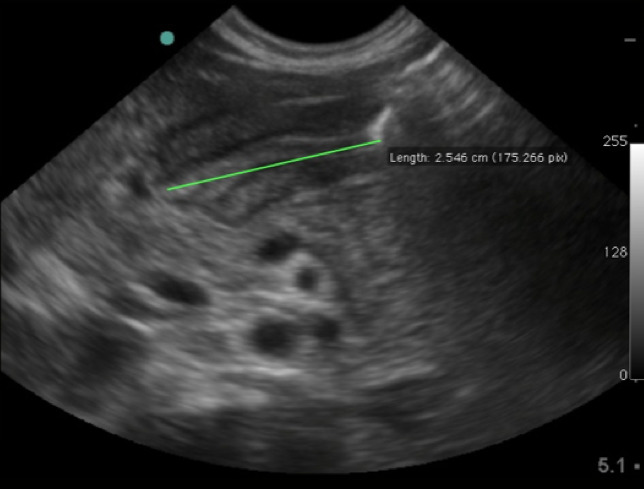

- Some experts also advocate the measurement of pyloric channel length. Unfortunately, there is no agreement for a firm cutoff for normal. In general, anything over 18mm should be considered abnormal.

- Figure 8. Elongated pyloric channel (25mm) consistent with stenosis